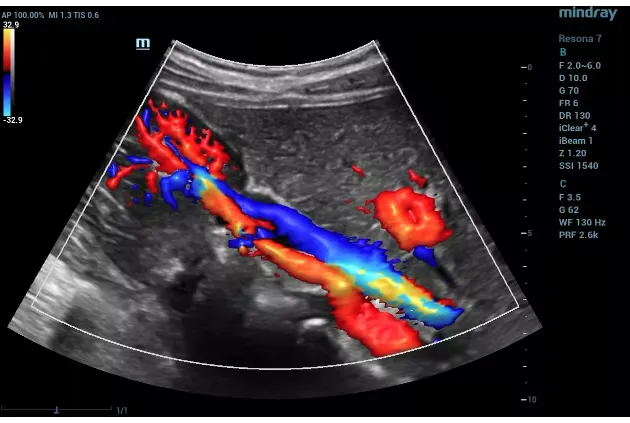

Carotid Doppler Ultrasound: Stroke Prevention Guide

How carotid Doppler ultrasound detects stroke risk by measuring neck artery blood flow. Who needs screening and what stenosis percentages mean.

Doppler Ultrasound for DVT: Detection & Accuracy

How Doppler ultrasound detects blood clots in deep veins. Symptoms that trigger testing, accuracy, Dubai-specific DVT risks, and treatment after diagnosis.

Doppler Ultrasound in Pregnancy: Fetal Blood Flow

Fetal Doppler explained: what it measures, when it's done, normal vs. abnormal readings, and why it's essential for high-risk pregnancies.

Doppler Ultrasound Cost in Dubai: Prices by Type (2026)

Doppler ultrasound pricing in Dubai by type: carotid, venous, arterial, renal, and pregnancy Doppler. Insurance coverage and DCDC pricing included.

Renal Doppler Ultrasound: Kidney Blood Flow Guide

How renal Doppler ultrasound evaluates kidney blood flow: renal artery stenosis detection, transplant monitoring, and who needs this test.

Peripheral Vascular Disease: Doppler Diagnosis Guide

How Doppler ultrasound diagnoses peripheral vascular disease: symptoms, ABI index, arterial mapping, and Dubai's diabetes-PVD connection.